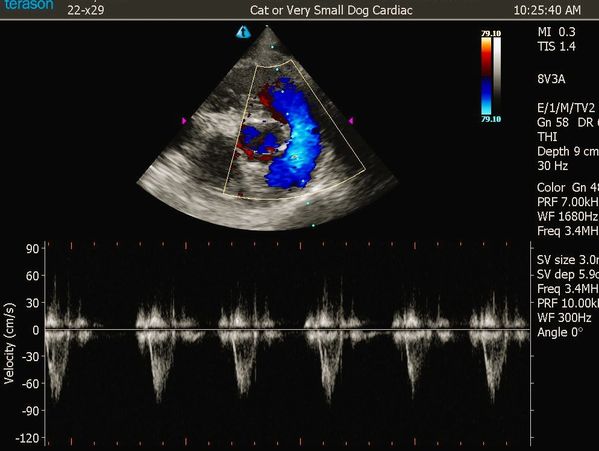

We perform full Doppler echocardiograms on every heart case, ensuring a detailed look at cardiac function and structure. Each study is guided in real time by an Oncura professional sonographer for top-quality results, and every scan is interpreted by a board-certified Oncura cardiologist for accurate, actionable insights.

Franimal’s Solutions proudly utilizes advanced imaging technology and telehealth support from Oncura Partners. Oncura provides us with state-of-the-art ultrasound equipment and real-time remote sonographer guidance for echocardiograms.

All cardiac imaging is interpreted by Oncura’s team of board-certified veterinary cardiologists, ensuring every patient receives a specialist-level evaluation. This